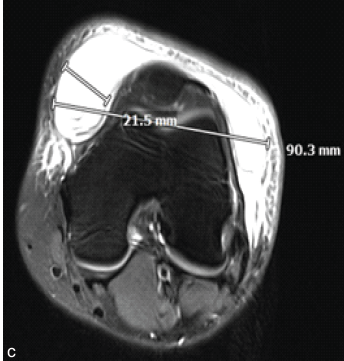

Arthroscopic Treatment of a Large Traumatic Morel-Lavallée Lesion of the Knee in a Young Female Athlete: A Case Report

Stefan W. Fleps , Allison R. Terry , Augustus C. Demanes , Michael A. Terry

………………………………p.157-161